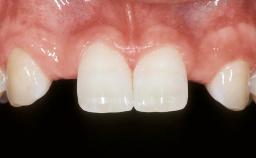

In September 2004, a 38-year-old female patient, a nonsmoker, was referred to our clinic for the replacement of the missing left central maxillary incisor (tooth 21),which had been removed two months before the initial appointment due to a vertical root fracture. The dental patient history revealed that the tooth in question had supported a ceramo-metal crown for more than ten years before the root fracture occurred. Implant therapy (single-tooth replacement) was considered the first therapeutic choice, as the neighboring teeth did not require significant restoration. The patient was in good general health, and her medical history revealed no significant findings.